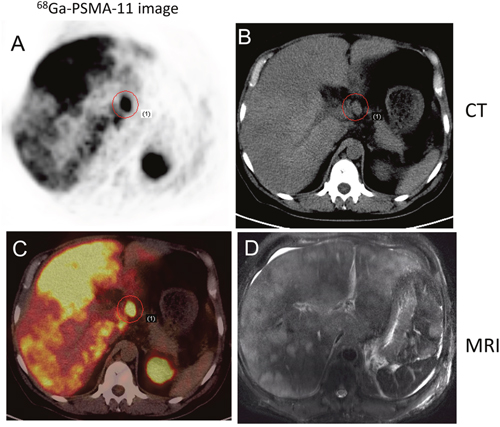

In 29 patients with bone metastasis, SUVmax ranged from 3.00 to 124.71 (27.57 ± 27.46). In 3 patients with stable disease, the PSA values ranged from 0.01 to 0.07 ng/ml, and no 68Ga-PSMA-11 uptake was observed, including into osteoblastic bone lesions. Of the 22 patients with treatment-naïve PCa, 17 had multiple lymph node and bone metastases. Based on these findings, these patients initially received hormonal treatment and radiotherapy or chemotherapy. For those with only pelvic lymph node positivity, radiotherapy was considered depending on the magnitude of PSA decline after hormone deprivation. In one patient with spinal cord involvement (SUVmax = 124.71), multiple lymph node and bone metastases were found in 68Ga-PSMA-11 images (Figure 3). In addition, 68Ga-PSMA-11 PET/CT newly detected lung metastasis in 5 patients and liver metastasis in 4 patients (Figures 4 and 5). In total, 17 patients with treatment-naïve PCa were upstaged after 68Ga-PSMA-11 PET/CT.

Figure 5: 68Ga-PSMA-11 PET/CT versus T2WI MRI in a 52-year-old patient with progressive disease. PCa was confirmed by lymph node aspiration; the serum PSA level was >10,000 ng/ml at the time of imaging. 68Ga-PSMA-11 PET/CT detected multiple lymph node and liver metastases. A. Transverse image. B. CT. C. Multiple sites of focal uptake in the liver. D. MRI.